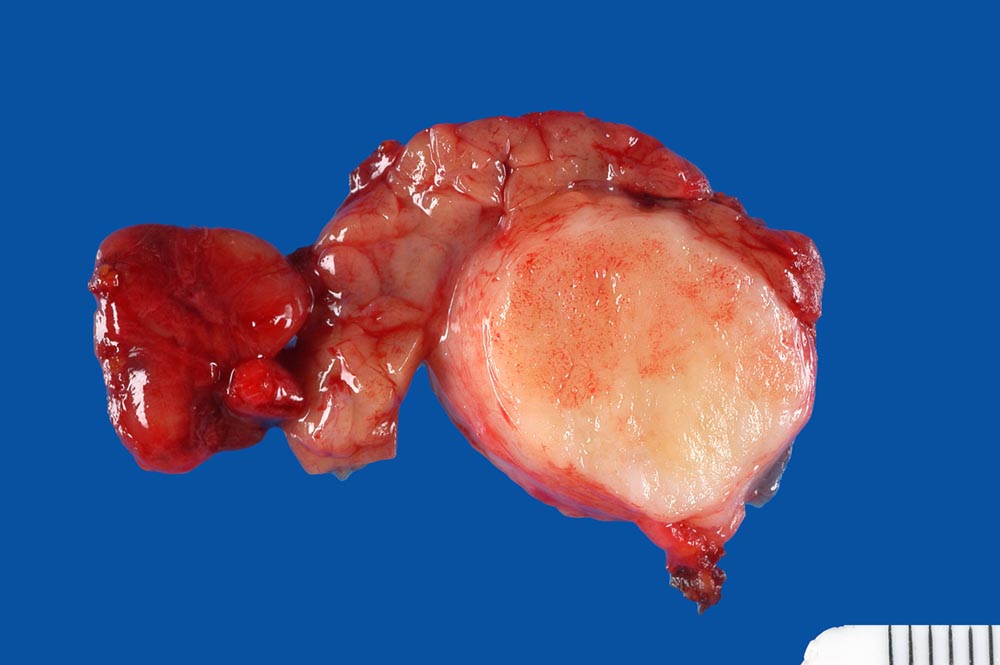

Pleomorphes Adenom der Glandula submandibularis

Innerhalb des makroskopisch unauffälligen Speicheldrüsengewebes findet sich ein bekapselter solider weissglänzender Tumor von 2cm Durchmesser.